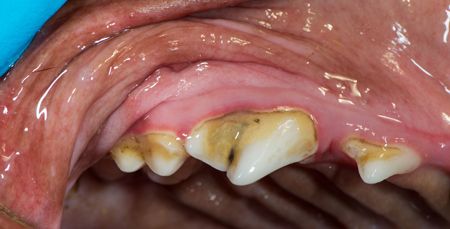

One of your veterinary clients has brought in Rylee for her annual check-up. She is a 3-year-old female German short-haired pointer. You flip her lip, take a gander and see her teeth as pictured below.

(Photos courtesy of Dr. Jan Bellows)

What do you think is going on?